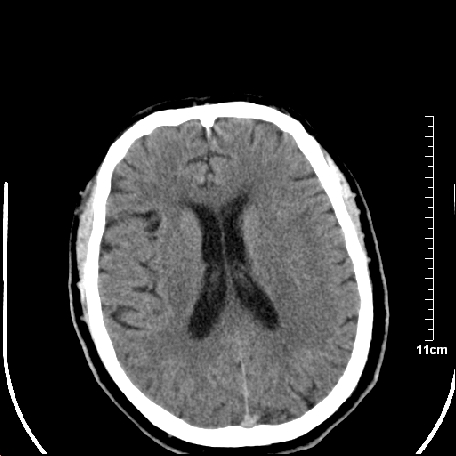

外伤患者,什么病,

外伤患者,没什么症状,

靠,老年脑,没什么病。

1.左额叶脑软化灶。

2.老年脑,基底动脉硬化迂曲。